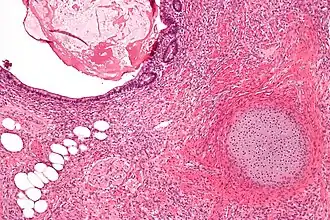

| Micrografia de um teratoma com componentes gastrointestinais (direita superior) cartilagem (direita inferior) e tecido adiposo (esquerda inferior). Tingido com Hematoxilina-Eosina. | |

O cisto dermóide é um dos tumores mais comuns do ovário e um exemplo de teratoma. Macroscopicamente é um tumor cístico preenchido por cabelos e material sebáceo. A parede interna do cisto tem aspecto de pele, com epiderme, folículos pilosos, glândulas sebáceas e sudoríparas. Geralmente, em uma área da parede mais saliente na luz do cisto e chamada promontório, encontramos vários outros tipos de tecido, que tipicamente derivam dos três folhetos embrionários. Alguns cistos dermóides parecem um atlas de histologia normal pela variedade de aspectos. Porém, os tecidos estão topograficamente desorganizados e agrupados sem nenhuma 'lógica'. Em diversas áreas podemos reconhecer estruturas organóides, como a que lembra víscera oca, com musculatura lisa em duas camadas e portanto ate esboço de inervação autonômica. Vemos tecido nervoso central (ectoderme) com áreas de gliose e até diferenciação para córtex cerebelar. Há vários tipos de epitélio de revestimento: escamoso, cilíndrico ciliado, com ou sem células caliciformes, e do tipo intestinal (endoderme). Há ainda glândulas mucosas, serosas e sero-mucosas (também da endoderme) e tecidos de linhagem conjuntiva como músculo liso e osso (mesoderme). Em suma, qualquer tecido normal pode estar presente.